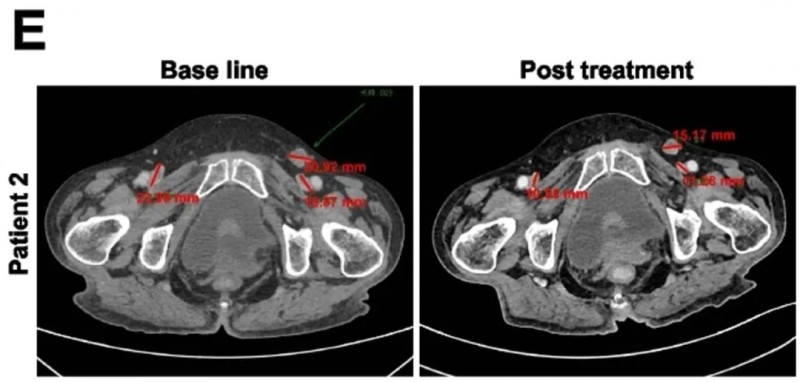

该研究共纳入8例晚期难治性患者(7例卵巢癌、1例间皮瘤),所有患者均至少接受过2种标准治疗(如化疗、靶向药)后复发或进展,且经病理确认肿瘤细胞MSLN表达≥15%(MSLN为KT032的精准靶点)。

结果显示:8例患者疾病控制率达100%,无1例出现快速进展,意味着CAR-T细胞成功抑制肿瘤进展;其中2例实现“部分缓解”(肿瘤缩小≥30%),部分缓解率33.3%;4例达到“疾病稳定”(肿瘤未增大或略有缩小),6例肿瘤得到有效压制。生存数据同样亮眼,患者中位无进展生存期(PFS)达5.5个月,中位总生存期(OS)达10.5个月,远超同类患者预期生存时间。此外,部分患者治疗后癌抗原125(CA125)水平显著下降,整体治疗有效率远超传统方案。

值得关注的是,两位患者的疗效尤为突出:患者1肝转移灶缩小31%,且腹腔积液完全消失;患者2可测量病灶总最大直径缩小42%(详见下图)。

▲图源“BMC”,版权归原作者所有,如无意中侵犯了知识产权,请联系我们删除